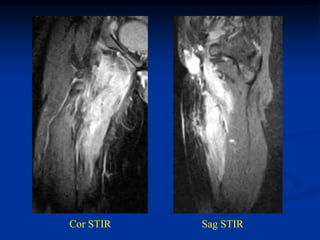

Case #276

64 year male with spindle cell lipoma proximal forearm

Sagittal T-1 MRI

Axial T-1 MRI

Axial proton density MRI